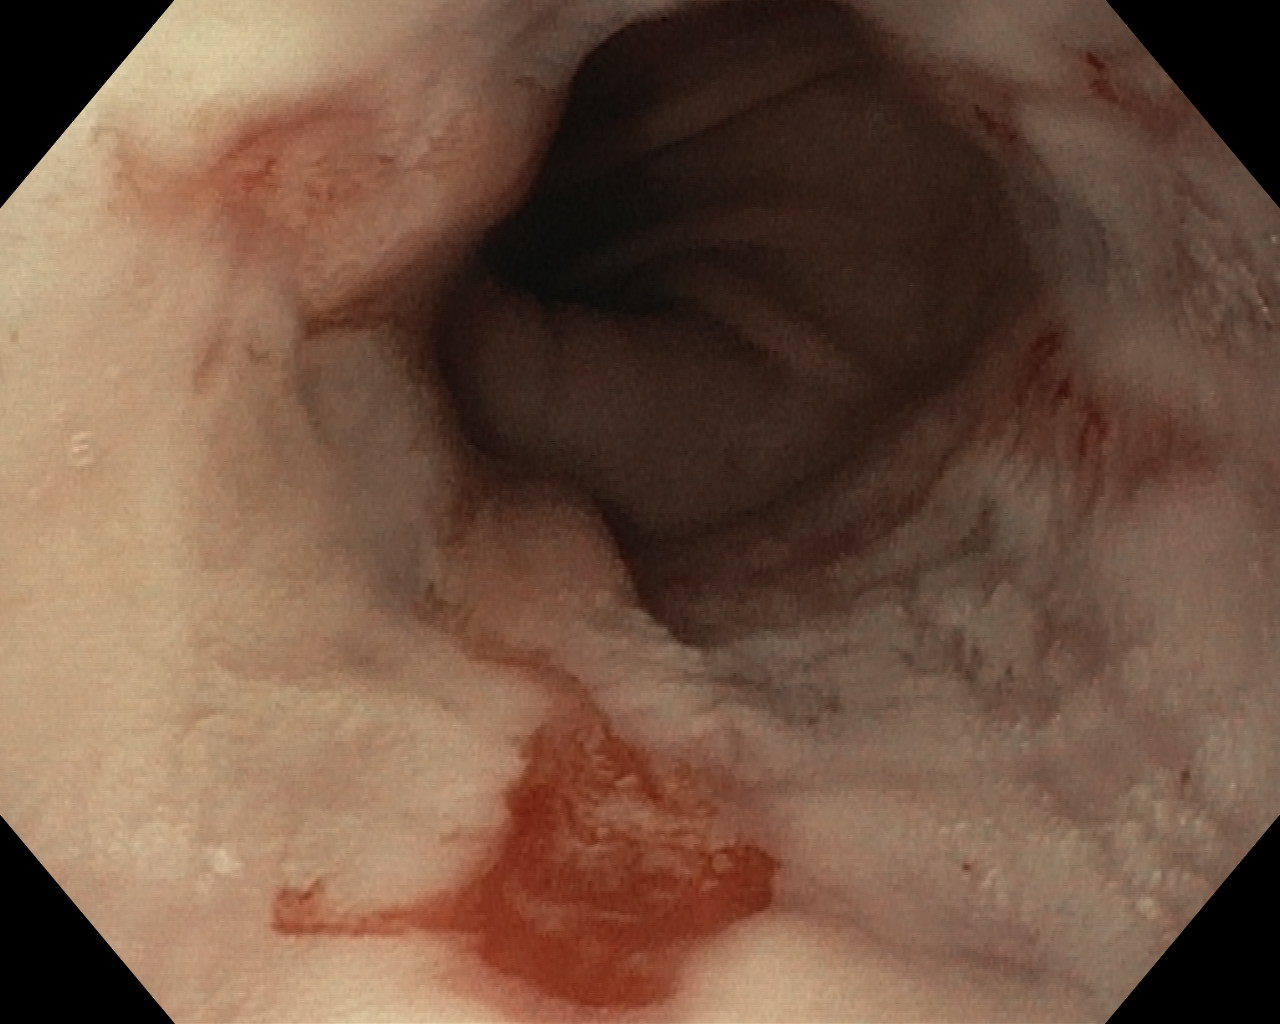

Obrazy endoskopowe

Choroba refluksowa